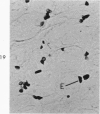

The beige mouse is a homolog of Chediak-Higashi syndrome, a disorder which is characterized by the presence of enlarged (anomalous) lysosomes in many cell types. In kidney, anomalous lysosomes are present in cells of the proximal convoluted tubules. In this study, the degradation of injected horseradish peroxidase (HRP) in lysosomes was studied in both the convoluted (S1-S2) and straight (S3) segments of the proximal tubules of beige and control (C57 B1) mice. Tissues were removed at intervals from 18 hours to 7 days after HRP injection. Peroxidase activity was visualized for light and electron microscopy by incubating sections in diaminobenzidine medium. No differences in the rate of degradation of HRP were demonstrable between anomalous lysosomes in S1-S2 cells of beige kidney and those in controls. In both animals, HRP was demonstrable in these lysosomes at 18 and 36 hours but not at 48 hours after injection. By electron microscopy, reaction product appeared as a flocculent precipitate distributed uniformly throughout the lysosome. In contrast to those of S1-S2 cells, lysosomes of beige S3 cells degraded HRP much more slowly than did those of control mice. In controls, HRP was demonstrable in S3 lysosomes at 18 hours but not at 48 hours after injection. In beige mouse kidney HRP was demonstrable in many S3 lysosomes at 48 hours, and it persisted in some lysosomes as long as 5 days after injection. These findings indicate that beige S3 lysosomes are defective in degrading protein. As reported recently, these lysosomes are also markedly enlarged and altered in content. They appear to arise as part of a renal lesion of unknown pathogenesis which is confined to the S3 segments of the proximal tubules. The slower rate of degradation of protein appears to be another manifestation of the alteration in these lysosomes.